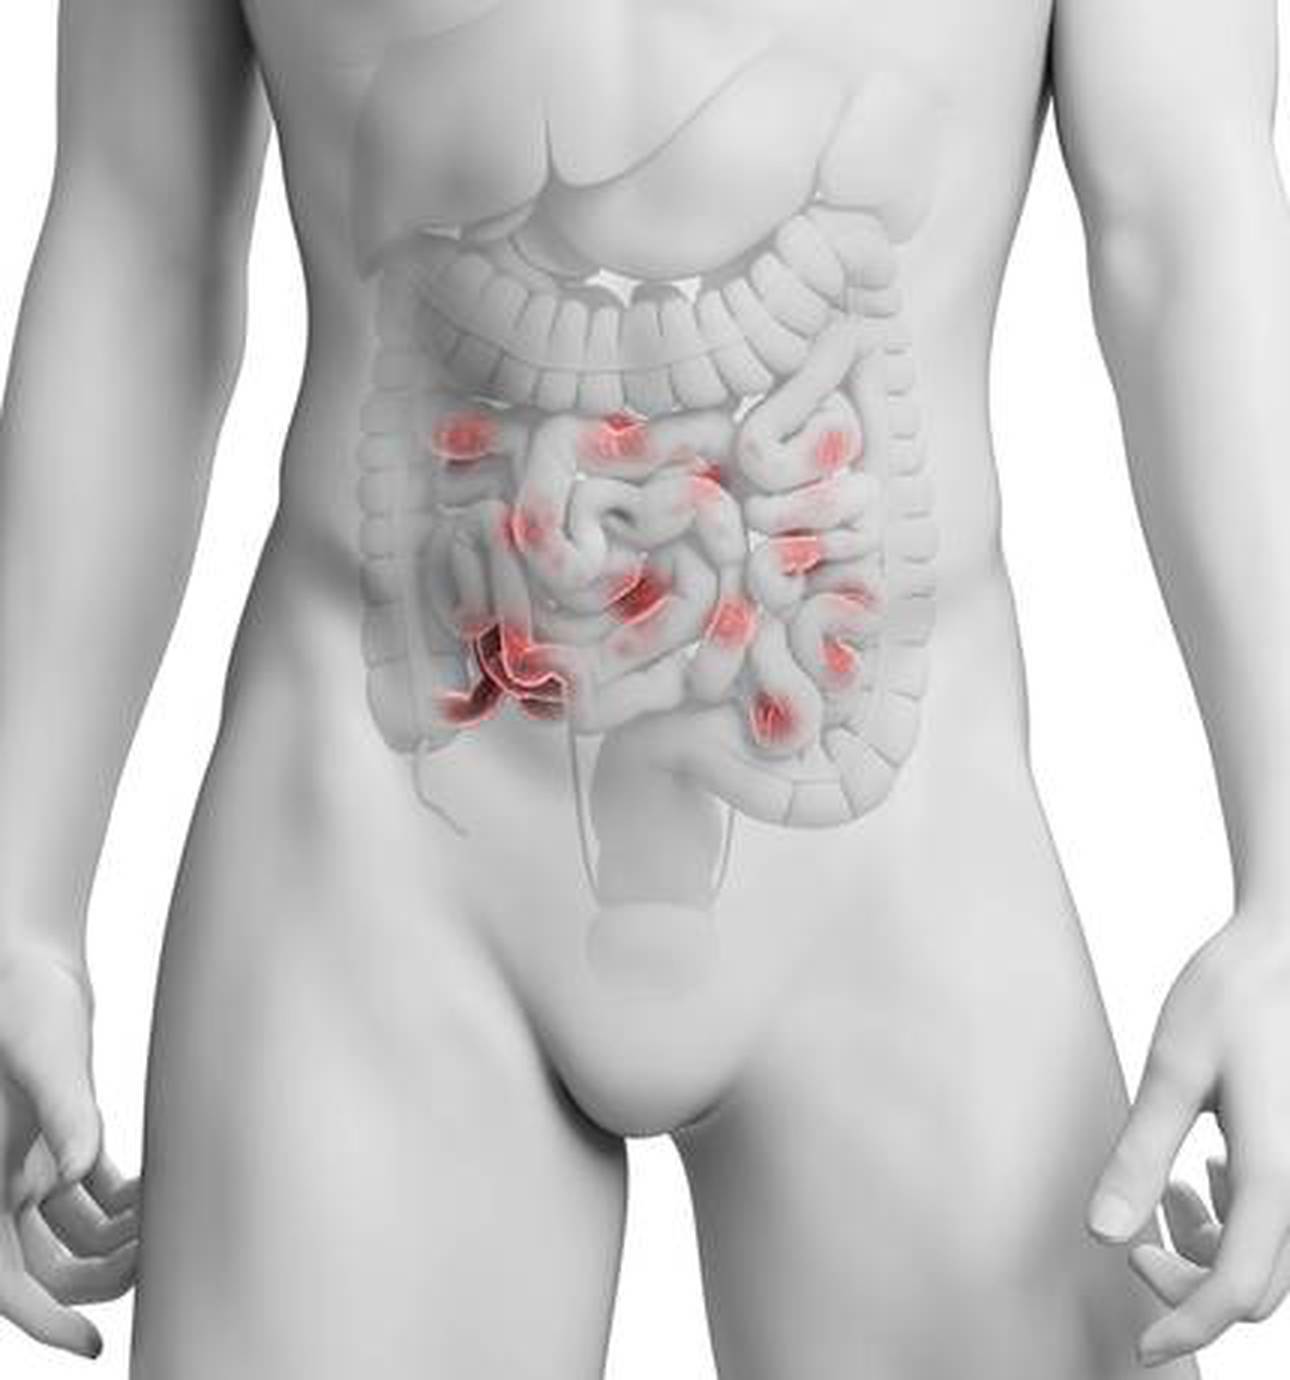

The unit is staffed by a multidisciplinary team that includes physicians, surgeons, highly specialised dieticians, nurses, and pharmacists who offer a comprehensive approach to IBD (Inflammatory Bowel Disease).

The St Mark’ Hospital IBD unit is a renowned worldwide specialist service, which attracts both national and international referrals. Patients are seen at both Northwick Park and Central Middlesex hospitals.

The inherited intestinal cancer syndromes are more commonly known as polyposis and Lynch Syndrome.